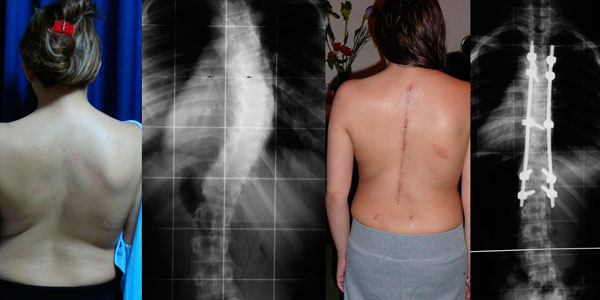

Mi mama y Yo comenzamos a notar que mi columna estaba torcida, consultamos varias clínicas y sinceramente el único que nos explico con detalle mi enfermedad fue el Dr. Carlos Cardenas, pareciera que otro médicos no conocían esta enfermedad. Mi diagnostico fue escoliosis idiopática del adolescente.

El único tratamiento para mi caso es con cirugía, tenia mucho miedo y me costo mucho decidir operarme.

Actualmente tengo 8 anos operada, y hago mi vida normal, hasta hago deporte, no tengo restricciones para nada.

Quería agradecer infinitamente al Dr. Carlos Cardenas, por el excelente resultado pero sobretodo por su profesionalismo.